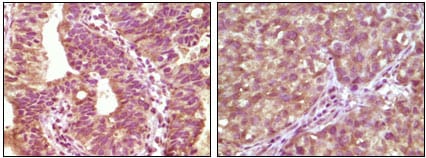

分类: 科研抗体货号: 20108别名: BRAF应用: IHC反应种属: Human

分类: 科研抗体货号: 20107别名: PR; NR3C3; PGR应用: IHC反应种属: Human